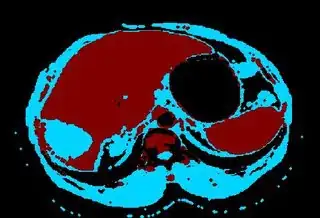

Below are some of the opened and segmented images. Of course there's more to be done in terms of

- separating out the liver region

- generalizing this to a large dataset

but hope this is at least a starting point.

You might be able to narrow down the region or interest by filtering out the darkest and the lightest regions from the segmented image. For this, use the k-means cluster centers, check for the extreme values (max and min) and remove the corresponding k values from the labeled image. Then you can look for large structures to the left of the result image. Worst case, you might get a hole on the left side when the extreme region filtering goes wrong. I've updated the code and results.